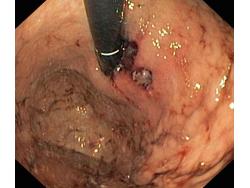

Krwawienie